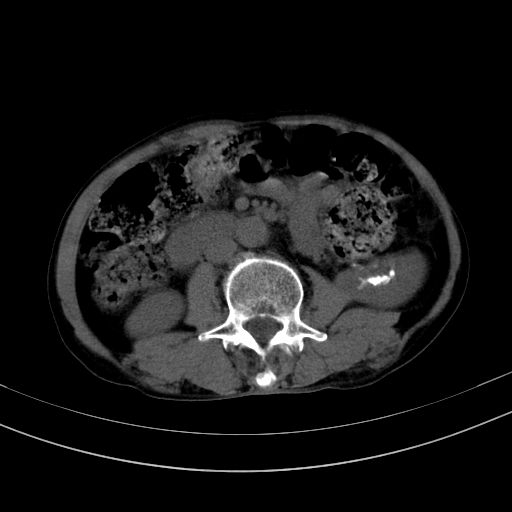

以下是引用37度在2010-1-9 14:37:00的发言:[br]1.双肾囊肿,左肾积水结石,.胆总管轻度扩张;[br]2.病灶在腹膜外,考虑纤维瘤。

以下是引用dyqct在2010-1-9 17:56:00的发言:[br]考虑:1.双肾囊肿,左肾积水结石、旋转不良。[br] 2.右侧腹直肌血肿或纤维瘤。[br]肠道准备不好。做个增强。